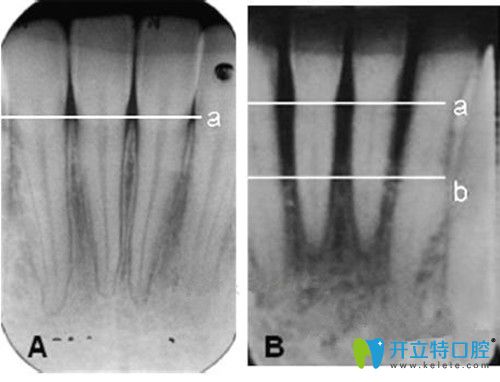

牙槽骨小于幾毫米不能種牙?怎么判斷牙槽骨薄,這篇就夠了

牙槽骨萎縮人工種植牙發(fā)布時間: 2025-04-25

種牙如種樹,骨量充足是種牙必備條件,如果你的牙槽骨萎縮,種牙前也許你需要先去植骨。那么怎么判斷牙槽骨薄?